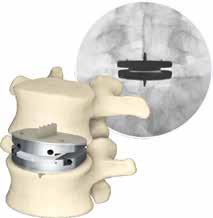

Total disc replacement (TDR) may be an alternative to spinal fusion for patients with cervical or lumbar herniated discs or degenerative disc disease.

The goals of total disc replacement surgery are to maintain segmental spinal motion, relieve pain, increase activity, restore disc height and proper spine curvature, and reduce post-operative recuperation time.

If you are experiencing neck or back pain and are considering surgery, isn't it worth your time to schedule an appointment with Dr. Jason E. Garber to nd out if motion preservation technology is an option for you?

Dr. Garber is one of Southern Nevada's most experienced spinal surgeons and a leader in arti cial disc replacement surgery.